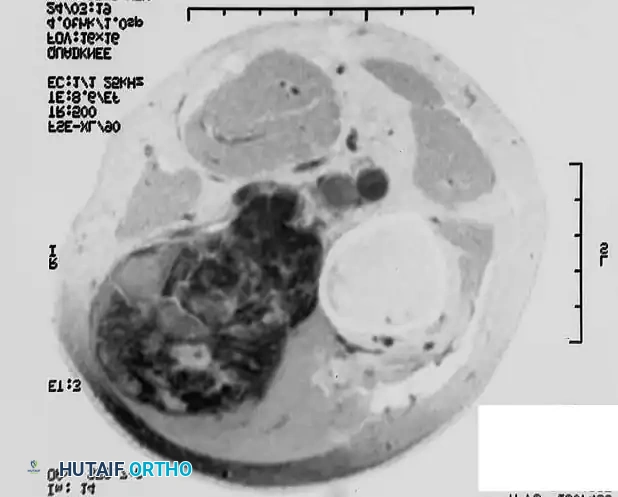

A: Preoperative MRI of a high-grade soft-tissue sarcoma in an 85-year-old man, demonstrating the tumor's intimate proximity to the distal femur and the superficial femoral vessels.

B: The resected gross specimen, excised with marginal margins due to the proximity of critical structures.

C: The surgical tumor cavity. Note the exposed distal femur and the skeletonized femoral vessels (arrow), representing areas of high risk for microscopic residual disease.

D: Brachytherapy application. Catheters are woven through a polyglactin 910 (Vicryl) mesh to maintain strict parallel spacing. The mesh is secured along the vessels and bone where margins were closest. The catheters exit through separate stab wounds, and the primary wound is closed over the array.